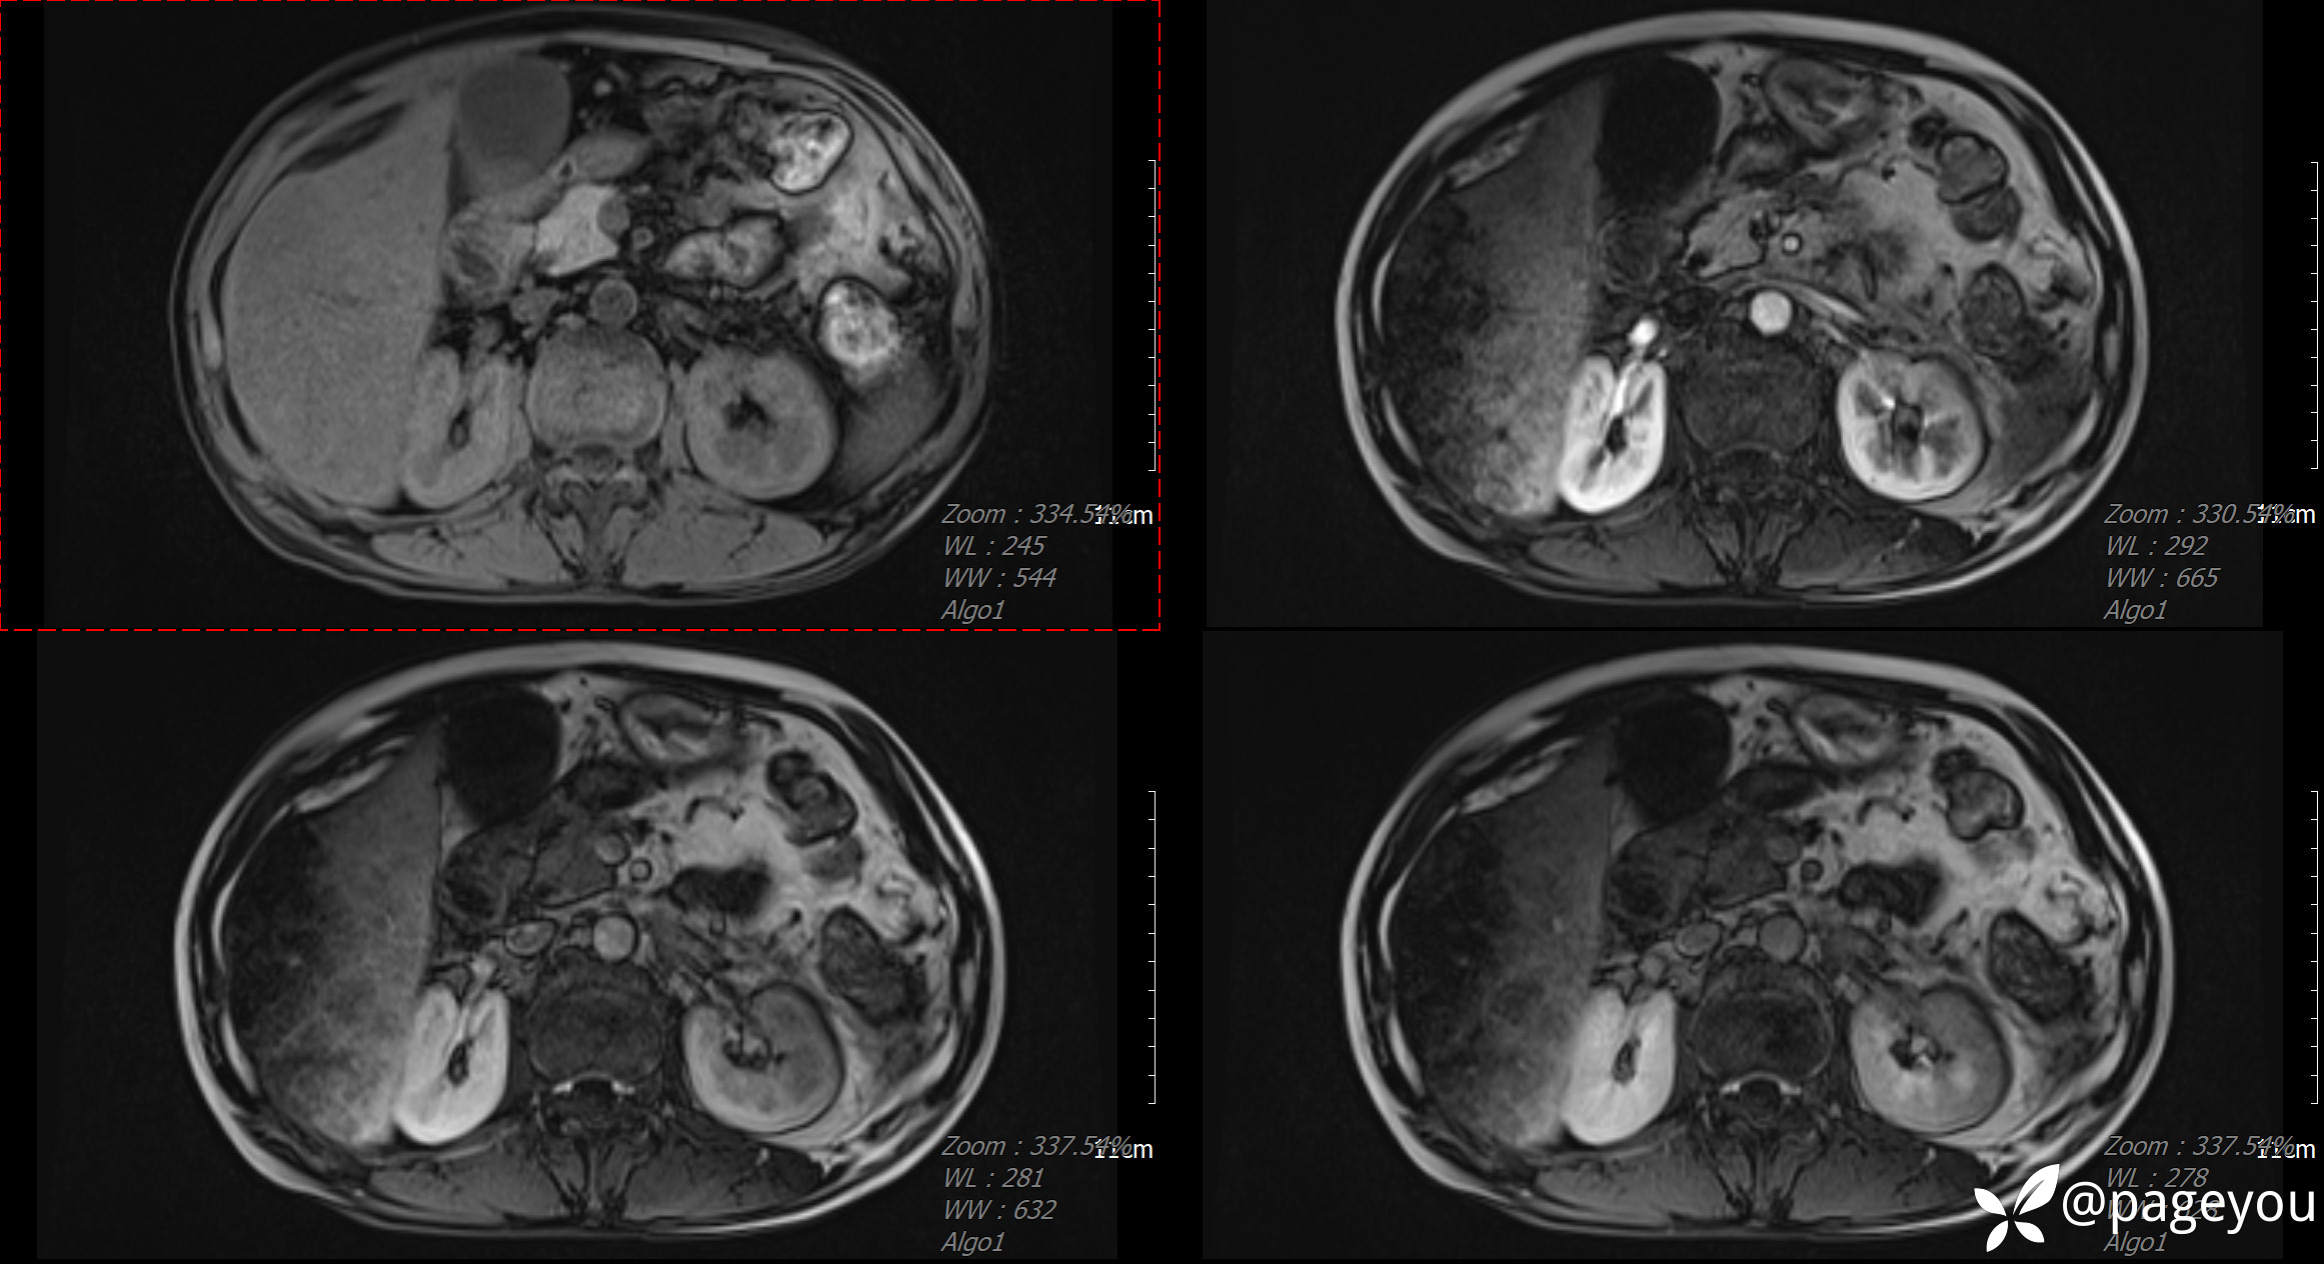

MRI检查: